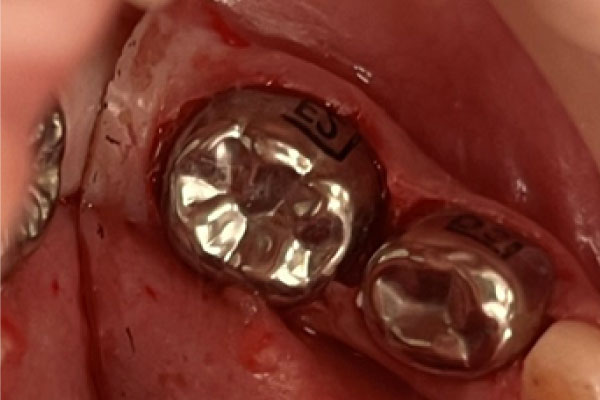

Наши работы

Показания для наркоза детям:

- Предстоящий большой объем стоматологического вмешательства;

- Невозможность проведения местного обезболивания (гиперактивный ребенок, не сидящий спокойно в кресле).